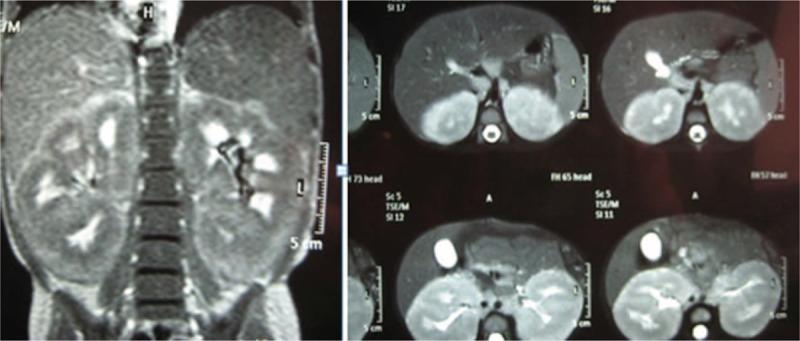

Renal enlargement at time of diagnosis of acute leukemia is very unusual. We here in report 2 pediatric cases of acute leukemia who had their renal affection as the first presenting symptom with no evidences of blast cells in blood smear and none of classical presentation of acute leukemia. The first case is a 4-year-old girl who presented with pallor and abdominal enlargement. Magnetic resonance imaging showed bilateral symmetrical homogenous enlarged kidneys suggestive of infiltration. Complete blood picture (CBC) revealed white blood count 11 × 10⁹/L, hemoglobin 8.7 g/dL and platelet count 197 × 10⁹/L. Bone marrow aspiration was performed, and diagnosed precursor B-cell ALL was made. The child had an excellent response to modified CCG 1991 standard risk protocol of chemotherapy with sustained remission, but unfortunately relapsed 11 month after the end of therapy. The second child was 13-month old, presented with pallor, vomiting, abdominal enlargement, and oliguria 2 days before admission. Initial CBC showed bicytopenia, elevated blood urea, creatinine, and serum uric acid, while abdominal ultrasonography revealed bilateral renal enlargement. Bone marrow examination was done and showed 92% blast of biphenotypic nature. So, biphynotypic leukemia with bilateral renal enlargement and acute renal failure was subsequently diagnosed. The patients admitted to ICU and received supportive care and prednisolone. Renal function normalized and chemotherapy was started. The child achieved complete remission with marked reduction of kidney size but, unfortunately she died from sepsis in consolidation phase of therapy. This case demonstrates an unusual early renal enlargement in childhood acute leukemia. Renal involvement of acute leukemia should be considered in child presenting with unexplained bilateral renal enlargement with or without renal function abnormalities and bone marrow examination should be included in the workup.

急性白血病诊断时出现肾脏肿大非常罕见。我们在此报告2例小儿急性白血病病例,他们以肾脏病变作为首发症状,血涂片未见原始细胞,也无急性白血病的典型表现。第一例是一名4岁女孩,表现为面色苍白和腹部肿大。磁共振成像显示双侧肾脏对称均匀肿大,提示有浸润。全血细胞计数(CBC)显示白细胞计数11×10⁹/L,血红蛋白8.7g/dL,血小板计数197×10⁹/L。进行了骨髓穿刺,诊断为前体B细胞急性淋巴细胞白血病。该患儿对改良的CCG 1991标准风险化疗方案反应良好,持续缓解,但不幸的是在治疗结束11个月后复发。第二个患儿13个月大,入院前2天出现面色苍白、呕吐、腹部肿大和少尿。初始CBC显示全血细胞减少,血尿素、肌酐和血清尿酸升高,而腹部超声显示双侧肾脏肿大。进行了骨髓检查,显示92%的原始细胞具有双表型性质。随后诊断为双表型白血病伴双侧肾脏肿大和急性肾衰竭。患者入住重症监护病房,接受支持治疗和泼尼松龙治疗。肾功能恢复正常并开始化疗。患儿实现完全缓解,肾脏大小明显缩小,但不幸的是她在治疗巩固期死于败血症。该病例显示了儿童急性白血病早期不寻常的肾脏肿大。对于出现不明原因双侧肾脏肿大、有无肾功能异常的儿童,应考虑急性白血病的肾脏受累情况,检查工作应包括骨髓检查。